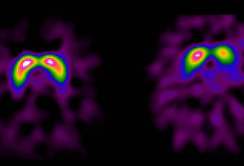

Das Parkinson-Syndrom stellt eine heterogene Gruppe von langsam fortschreitenden, neurologischen Erkrankungen dar, das auf das Absterben der Dopamin-produzierenden Nervenzellen in der Schwarzen Substanz – einer Struktur im Mittelhirn – zurückzuführen ist. Das Zellsterben führt zu einem Mangel des wichtigen Botenstoffes Dopamin und schließlich zur Entstehung der meisten, zentralen Symptome der Krankheit. Dazu zählen allgemeine Bewegungsarmut, Muskelsteifheit, Ruhe-Zittern sowie Gang- und Gleichgewichtsstörungen. Die Ursache des Zellschwundes in der Schwarzen Substanz wurde – mit Ausnahme einer erblichen Variante – bislang nicht gefunden. Parkinson ist deshalb bis heute nicht kausal, sondern ausschließlich symptomatisch behandelbar: Beispielsweise durch die Gabe von Medikamenten (Levodopa), die zu einer Erhöhung des Dopamin-Angebots im Gehirn führen sowie auch durch neurochirurgische Eingriffe. Parkinsonpatient:innen zeigen bis zehn Jahre nach der Diagnose gute Therapieerfolge, doch im weiteren Verlauf kommt es zu vermehrten Gleichgewichtsstörungen und Stürzen, einem Abbau der geistigen Leistungsfähigkeit und einer Zunahme nicht-motorischer Störungen.

Zahlreiche Studien, unter anderem auch aus Innsbruck, belegen, dass viele Parkinson-Patient:innen schon vor dem Auftreten der ersten motorischen Symptome andere Dysfunktionen entwickeln. Im Frühstadium werden etwa die chronische Obstipation (Verstopfung), aber auch Stimmungsstörungen mit Depressivität oder Panikattacken beobachtet. Aber auch die Störung des Geruchssinns und die nächtliche REM-Schlafstörung können frühe Indikatoren für das Parkinson-Syndrom sein. „Mindestens 50 Prozent der Patient:innen zeigen bis zehn Jahre vor Beginn der Krankheit derartige Symptome“, bestätigt Prof. Poewe ein Forschungsergebnis aus einer, in Zusammenarbeit mit Forscherkolleg:innen in Barcelona durchgeführten Untersuchung. Die „prämotorische“ Phase kann Monate bis Jahre in Anspruch nehmen und bildet somit ein wichtiges Zeitfenster für die Frühdiagnostik. Diagnostisches Potenzial liegt aber auch in der Bildgebung: So konnte in mehreren Studien die prädiktive Relevanz von Ultraschallmerkmalen im Mittelhirn bestätigt werden.